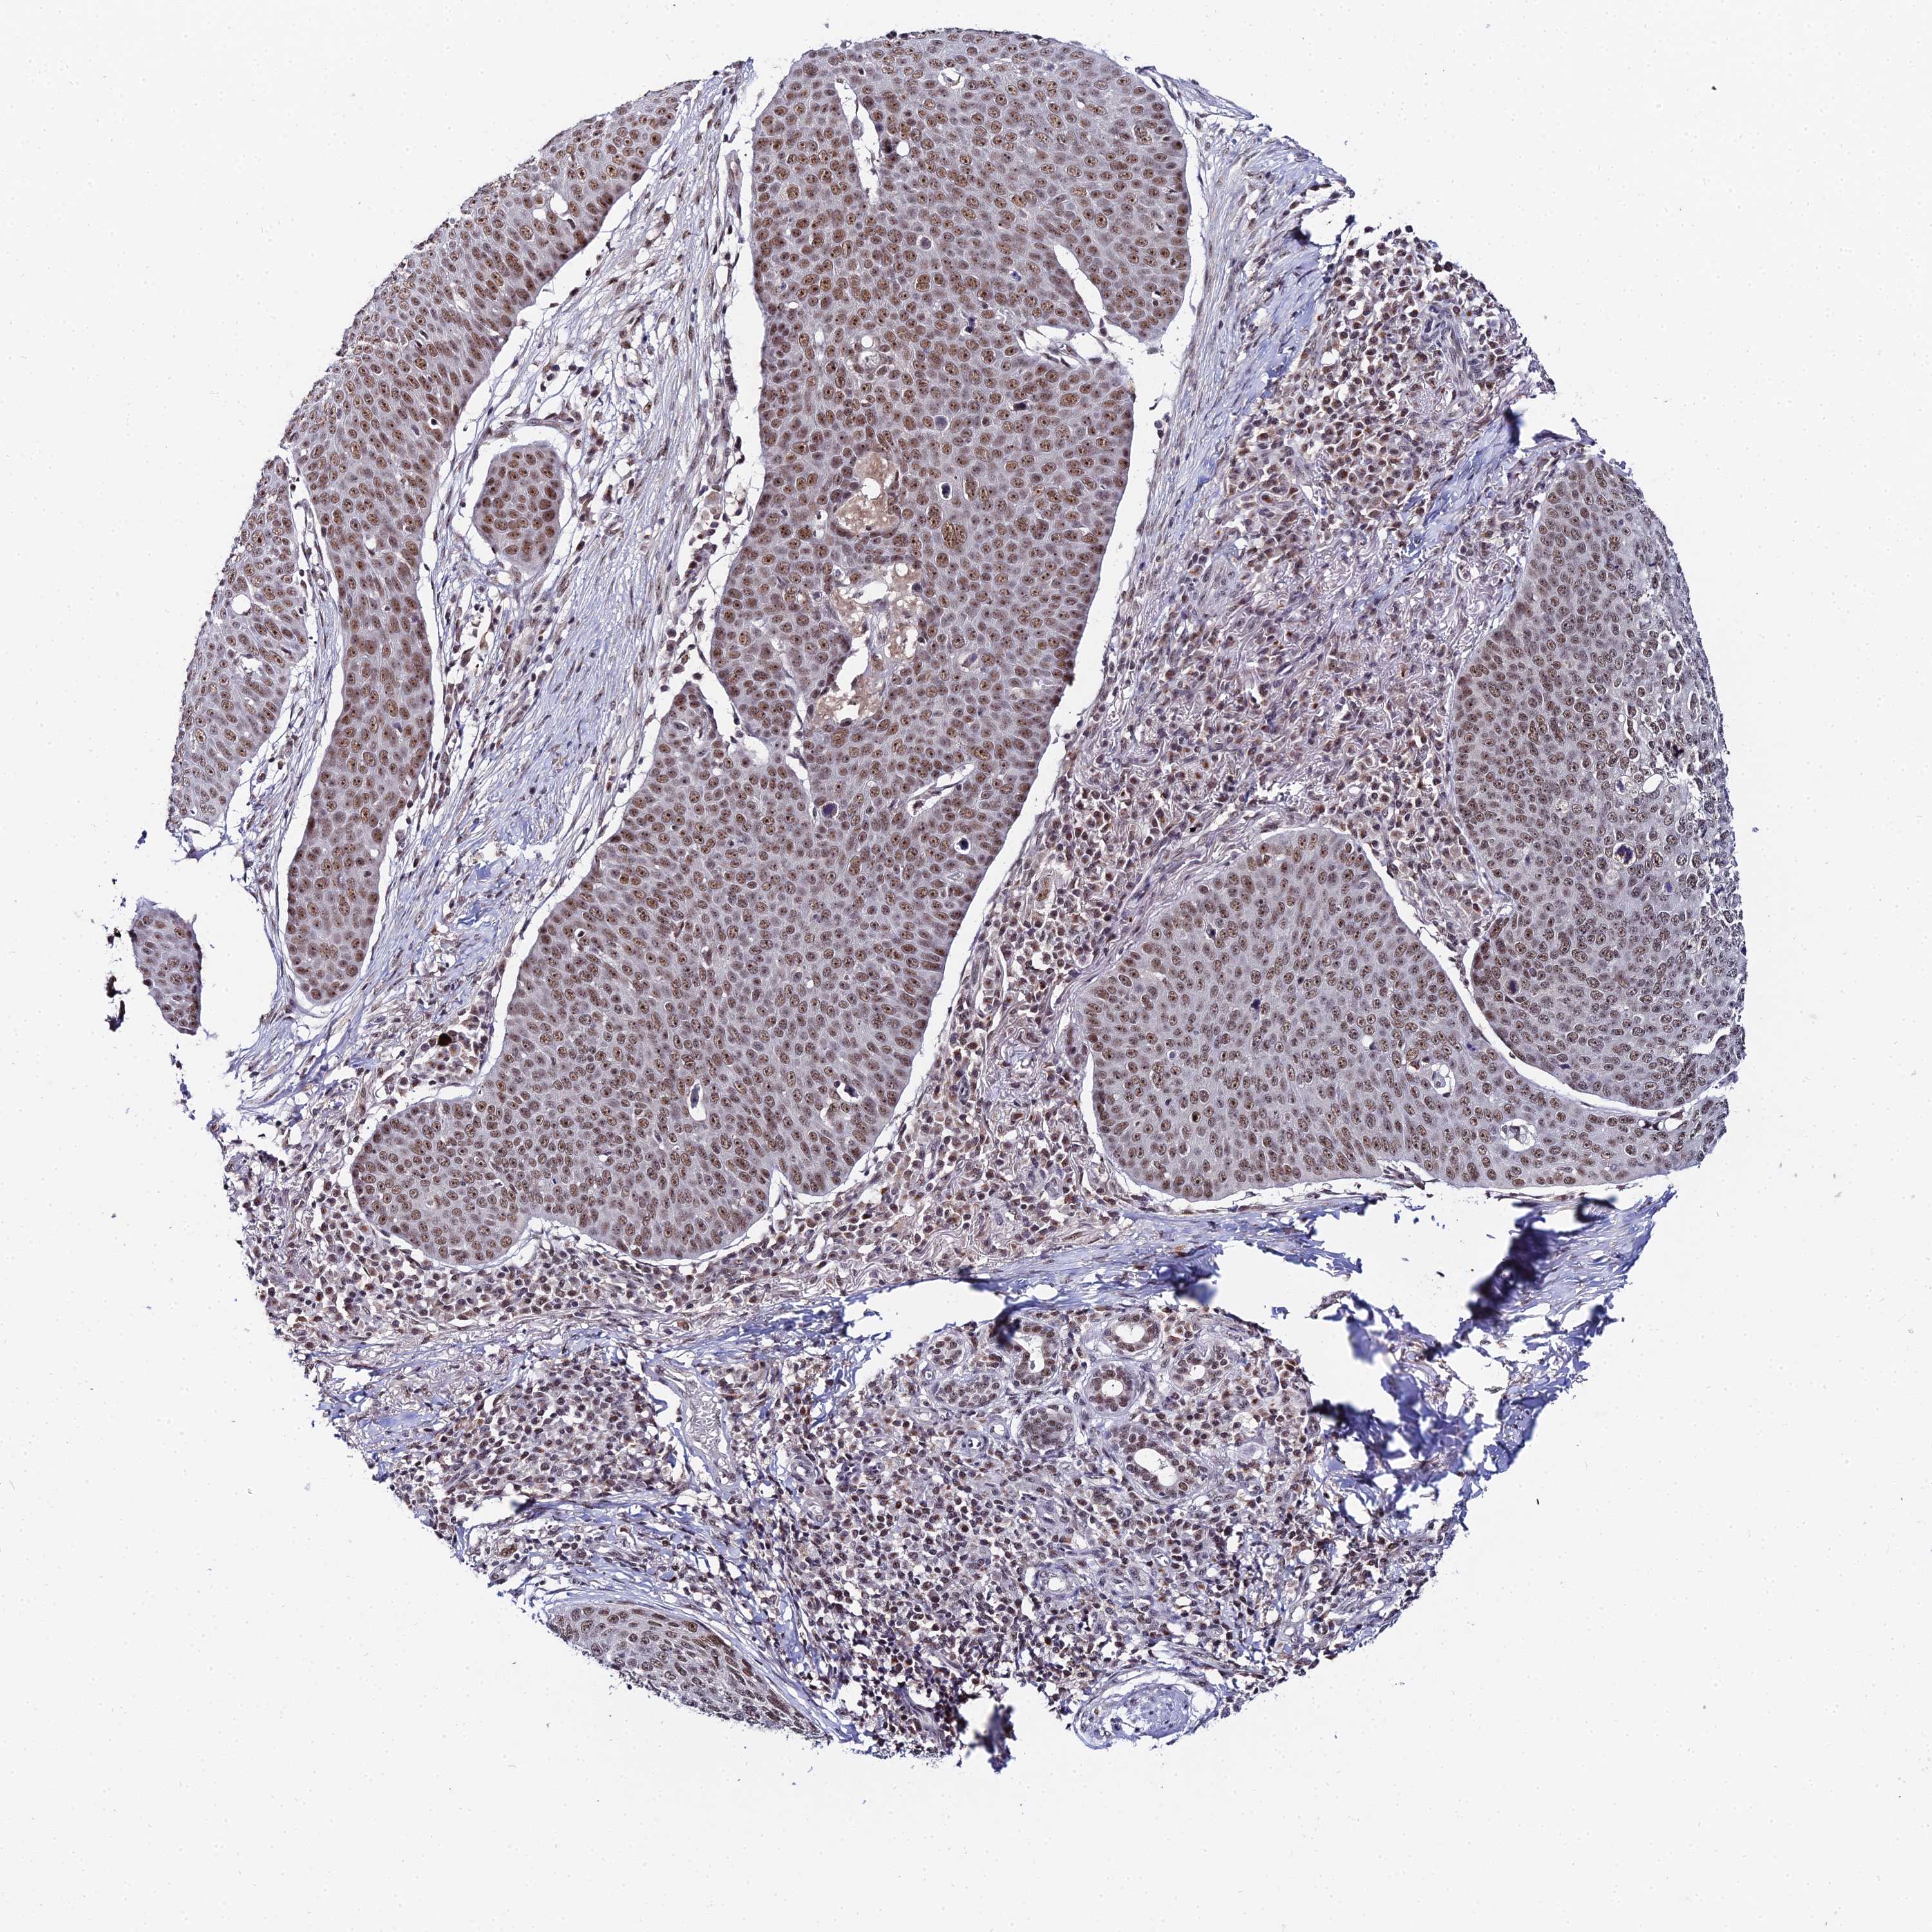

SKIN CANCER - Protein expressioni

A mouse-over function shows sample information and annotation data. Click on an image to view it in a full screen mode. Samples can be filtered based on level of antibody staining by selecting one or several of the following categories: high, medium, low and not detected. The assay and annotation is described here.

Each image is clickable and will lead to virtual microscopy that enables deeper exploration of all samples and also displays staining intensity scores, fraction scores and subcellular localization as well as patient and tissue information for each sample.

Antibody HPA020485

Staining

High

Intensity

Strong

Quantity

>75%

Location

Nuclear

Basal cell carcinoma